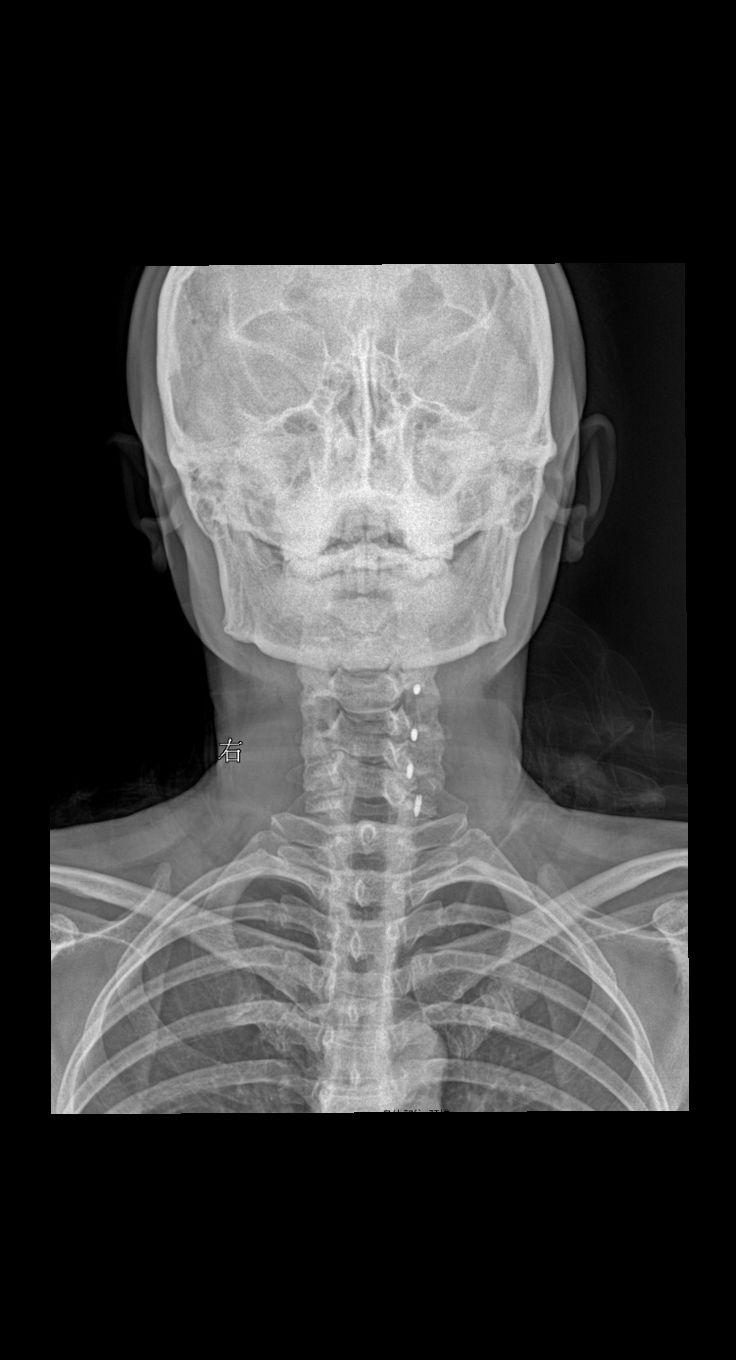

颈椎术后,疼痛就诊 45岁